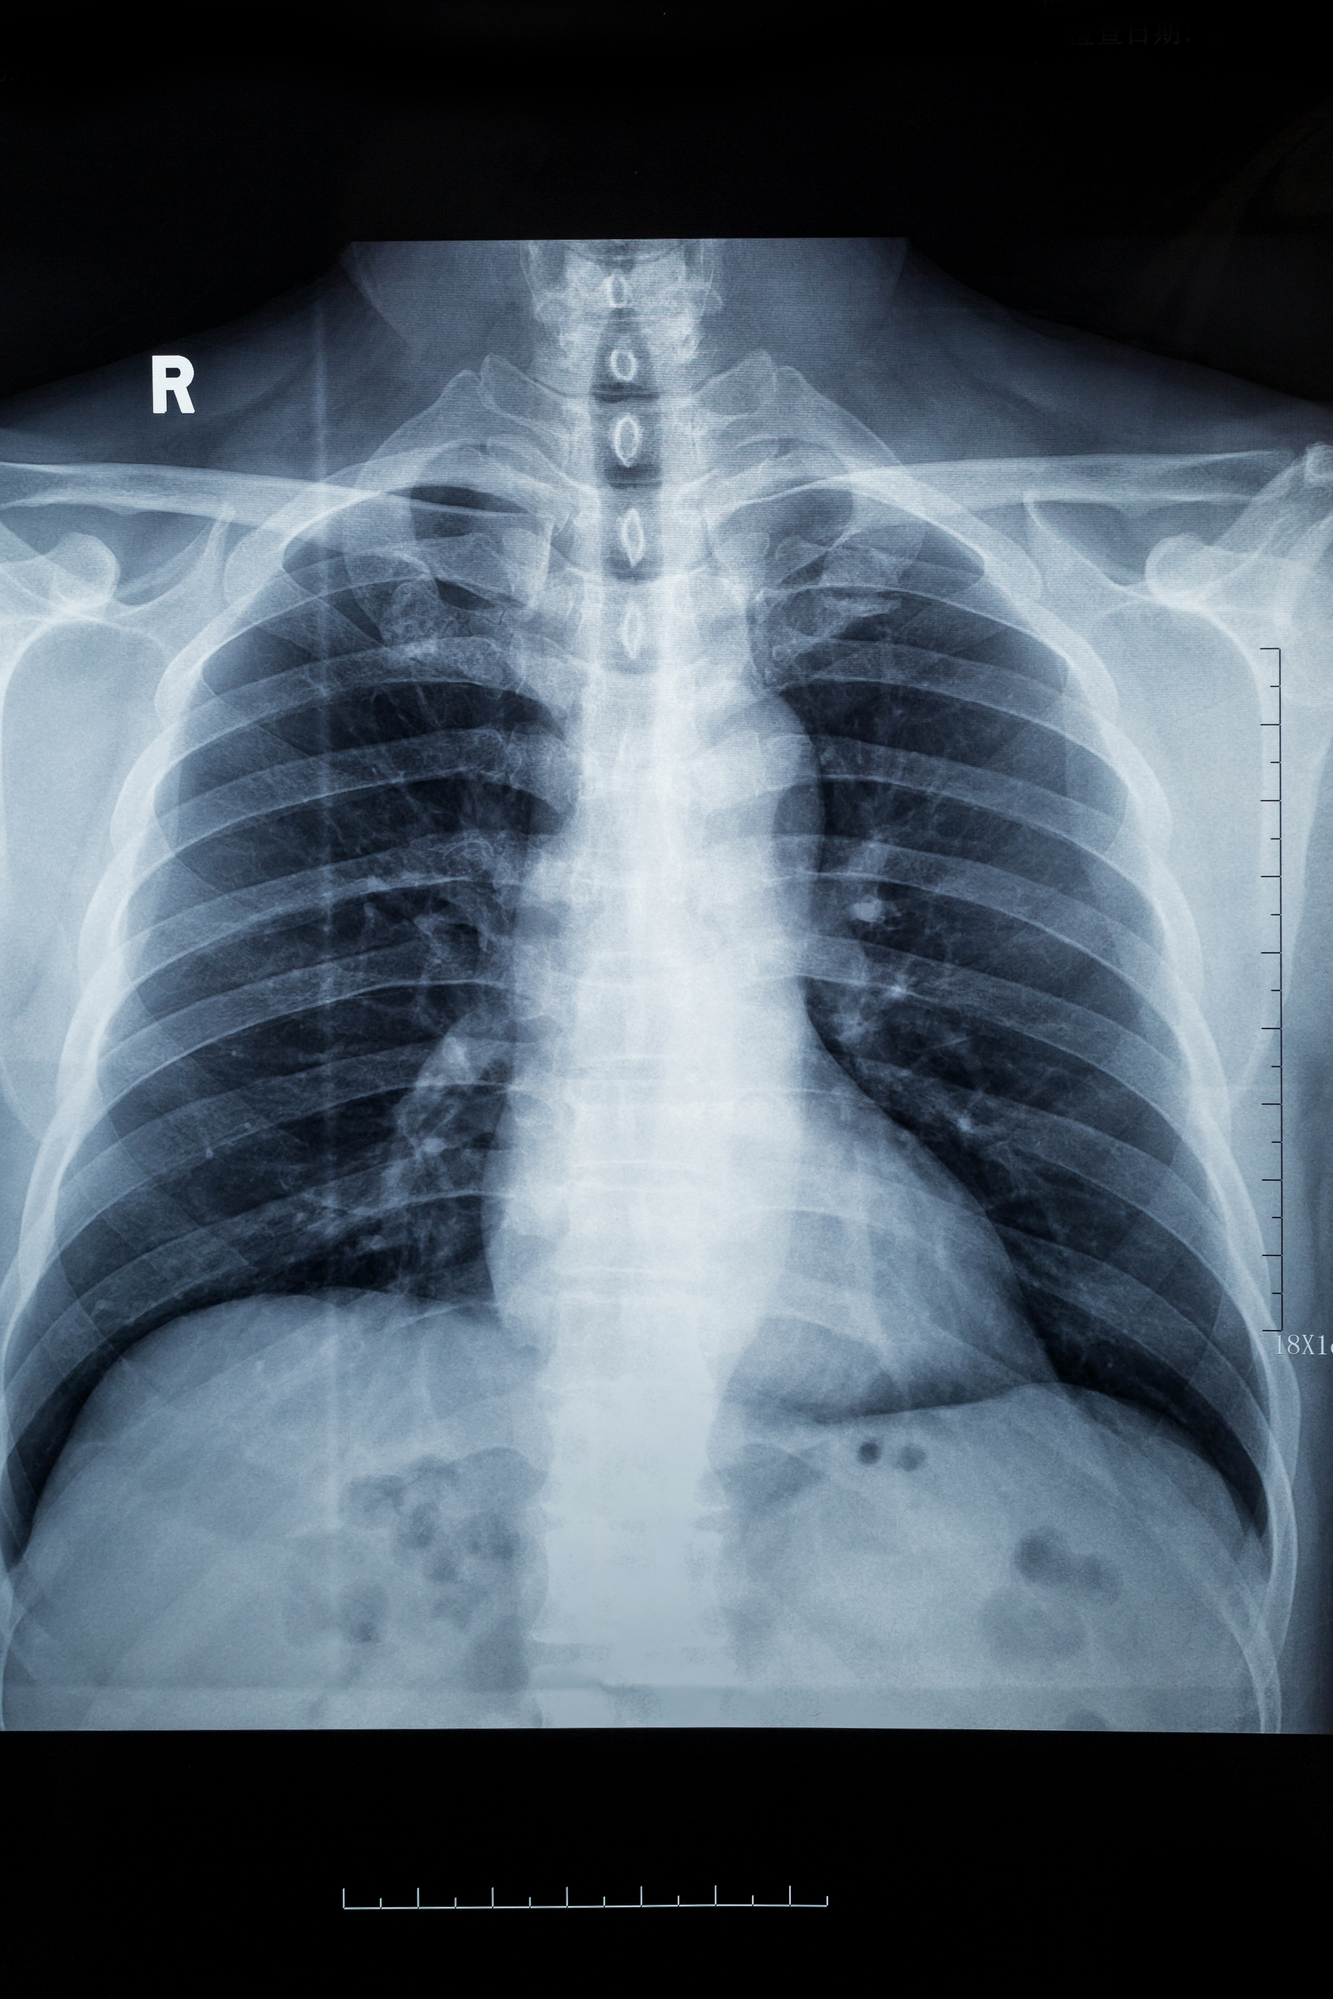

How do CT Scans Work?

CT scans use a narrow X-ray beam to provide doctors with a series of images of your body from different angles. A computer then uses these images to piece together a detailed view of your organs and other tissues. This can help medical professionals make better choices on the types of procedures, surgeries, and treatment options that may be available.